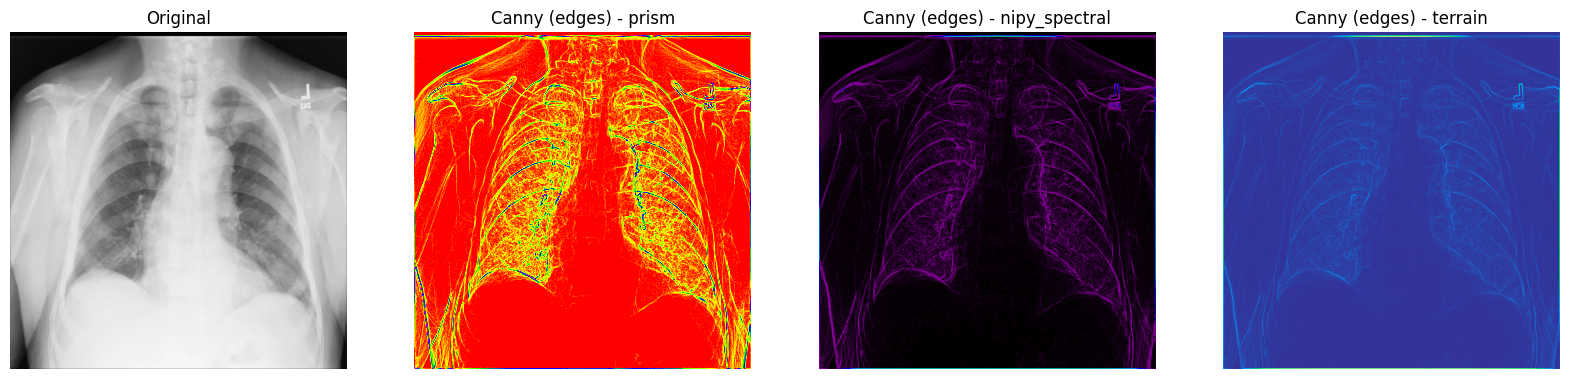

Canny 滤波器

您还可以考虑使用另一种用于边缘检测的著名滤波器,称为 Canny 滤波器。

首先,应用 高斯 滤波器来消除图像中的噪声。在本例中,您使用的是 傅里叶 滤波器,它通过 卷积 过程平滑 X 射线图像。接下来,对图像的每个轴应用 Prewitt 滤波器 来帮助检测一些边缘 - 这将导致 2 个梯度值。与 Sobel 滤波器类似,Prewitt 算子也将两个 3x3 的卷积核矩阵(一个用于每个轴)应用于 X 射线图像,然后使用勾股定理计算两个梯度之间的幅度,并像之前一样对图像进行归一化。

1. 使用 SciPy 的傅里叶滤波器 - scipy.ndimage.fourier_gaussian(),使用较小的 sigma 值从 X 射线图像中去除一些噪声。然后,使用 scipy.ndimage.prewitt() 计算两个梯度。接下来,使用 NumPy 的 np.hypot() 计算梯度之间的距离。最后,像之前一样对重新缩放的图像进行归一化。

fourier_gaussian = ndimage.fourier_gaussian(xray_image, sigma=0.05)

x_prewitt = ndimage.prewitt(fourier_gaussian, axis=0)

y_prewitt = ndimage.prewitt(fourier_gaussian, axis=1)

xray_image_canny = np.hypot(x_prewitt, y_prewitt)

xray_image_canny *= 255.0 / np.max(xray_image_canny)

print("数据类型 - ", xray_image_canny.dtype)

数据类型 - float64

2. 绘制原始 X 射线图像以及使用 Canny 滤波器技术检测到的边缘图像。可以使用 prism、nipy_spectral 和 terrain Matplotlib 颜色映射来强调边缘。

fig, axes = plt.subplots(nrows=1, ncols=4, figsize=(20, 15))

axes[0].set_title("原始图像")

axes[0].imshow(xray_image, cmap="gray")

axes[1].set_title("Canny(边缘)- prism")

axes[1].imshow(xray_image_canny, cmap="prism")

axes[2].set_title("Canny(边缘)- nipy_spectral")

axes[2].imshow(xray_image_canny, cmap="nipy_spectral")

axes[3].set_title("Canny(边缘)- terrain")

axes[3].imshow(xray_image_canny, cmap="terrain")

for i in axes:

i.axis("off")

plt.show()